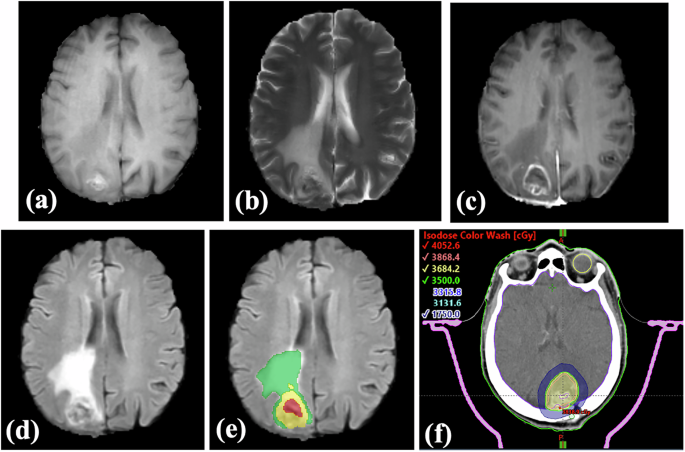

In this contribution, we present a unique BM dataset of cancer patients in Cyprus, which includes standard MRI sequences (T1W, T2W, T1-Contrast, FLAIR; see Fig. 1), the radiotherapy plan (RTP) and computed tomography (CT) scans, and detailed annotations of tumor subregions – specifically labels for the enhancing tumor, the edema, the necrotic region. Additionally, we provide two supplementary Excel files containing clinical evidence: one file includes essential demographic, clinical, and treatment-related information, offering valuable insights for medical analysis and AI-driven research, while the other file provides quantitative imaging data for each patient case.

Representative MRI scans of a patient displaying the brain in four imaging modalities: (a) T1-weighted, (b) T2-weighted, (c) post-contrast T1-weighted (T1-Contrast), and (d) fluid-attenuated inversion recovery (FLAIR). (e) Tumor subregions are delineated according to the BraTS annotation standards, with necrotic core (red), peritumoral edema (green), and enhancing tumor (yellow). (f) The radiotherapy overlaid on a computed tomography scan of brain tumor, illustrating dose distribution and anatomical structures involved in treatment.

The MRI scans, were processed using multiple segmentation methodologies, including the deep learning model DeepBraTumIA34, the nnU-Net35 model trained on the BraTS 2020 dataset, and the proprietary software Imalytics Preclinical36. Both DeepBraTumIA and nnU-Net models were used to automatically segment each MRI scan into three tumor subregions: enhancing tumor edema (T2/FLAIR hyperintensity) and tumor necrosis (see Fig. 1). In cases where patients had multiple metastases, DeepBraTumIA and nnU-Net were unable to detect all lesions. To address this limitation, a semi-automated segmentation method using Imalytics Preclinical36, was carried out. In this approach, tumors were initially manually delineated across several central slices of the 3D volume, followed by automatic detection across all slices using built-in algorithms of the software. The edema and necrotic tissue segmentations were performed manually by experienced professionals to ensure accuracy. In addition, the segmentation of white matter, grey matter, ventricle and cerebrospinal fluid components of normal brain tissue were automatically annotated using a geodesical information flows-based algorithm36 that is incorporated into the open-source toolkit NiftySeg. The segmentation outputs generated by DeepBraTumIA, nnU-Net and Imalytics Preclinical, were subsequently transformed into the BraTS space (Fig. 1e) to ensure accurate and reliable alignment with the corresponding MRIs. To guarantee consistency and clinical reliability, all segmentations were thoroughly reviewed and manually refined by a certified neuroradiologist (L.S.) with over 10 years of clinical experience. Open-source software ITK-SNAP 4.0.2 was used to visualize and verify the segmentation results during the revision process.